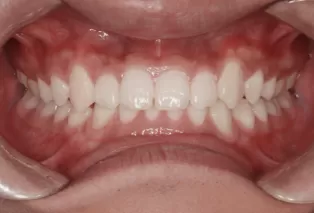

Intraoral photos after treatment